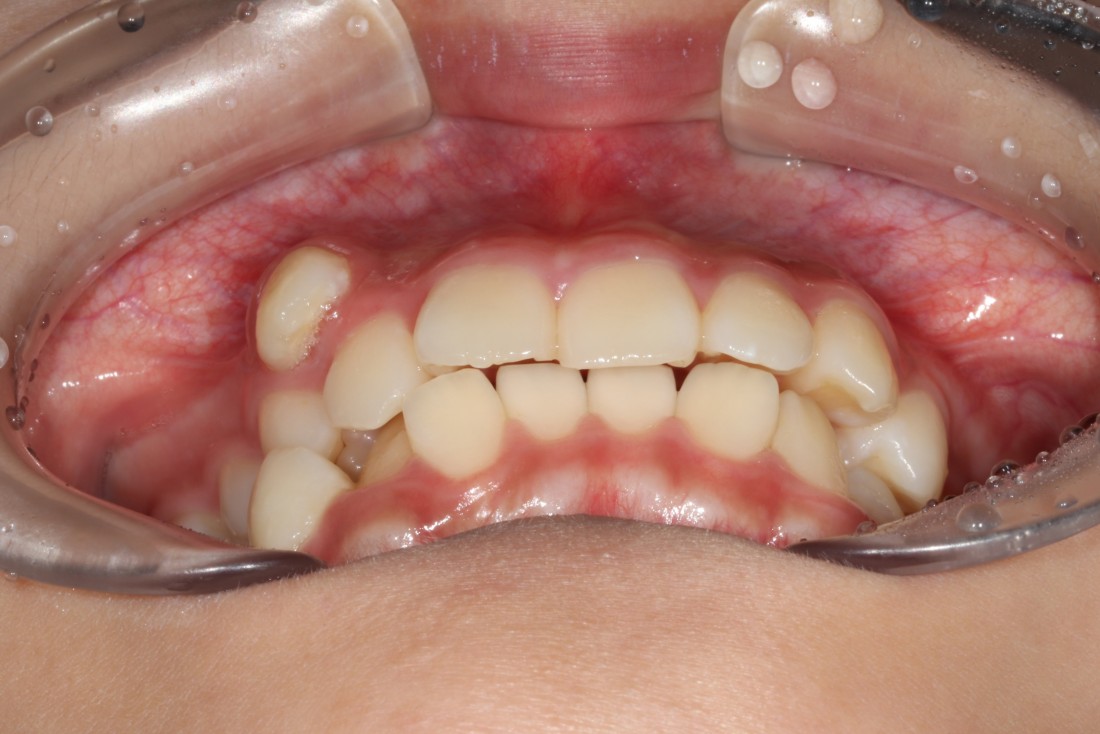

일반적으로 치아가 이동할 공간이

부족할 경우에 발치교정을 하게 됩니다.

발치 교정이 꼭 필요한 경우인데도

발치를 하지 않고 치아교정을 하게 되면

오히려 공간이 부족해 앞니가 더 튀어나오게 되고

입이 돌출입처럼 바뀌게 됩니다.